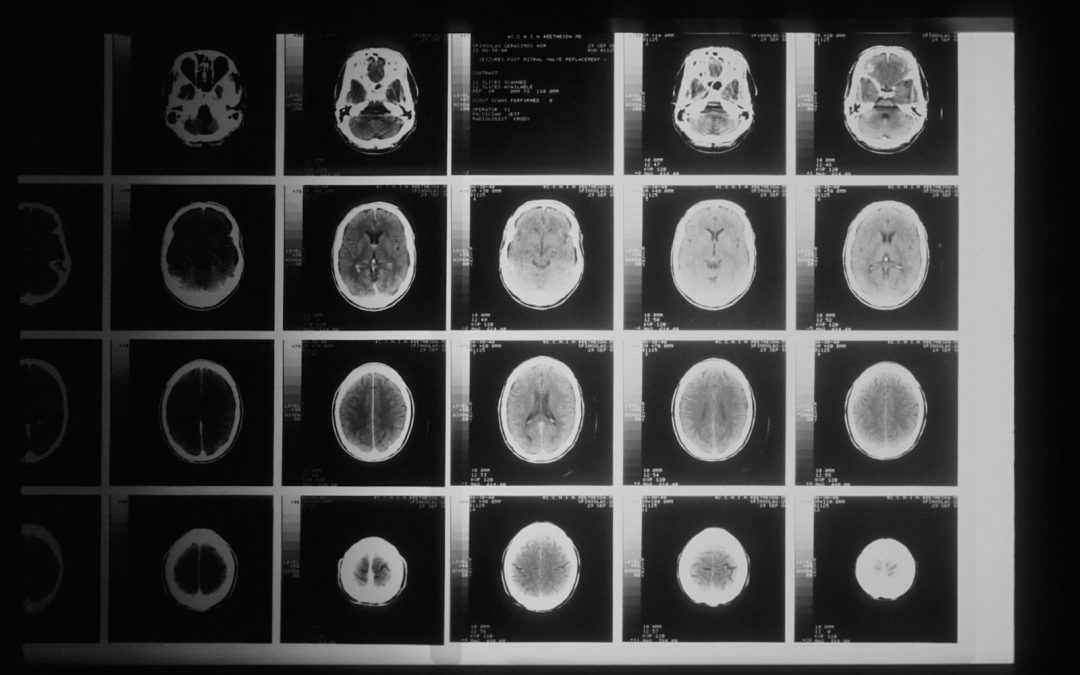

Additionally, TBIs are often missed because when one checks into the ER, medical practitioners mainly focus on immediate life-threatening problems like bleeding or skull fractures that need surgery. Many TBIs, especially mild ones, do not appear on routine scans immediately and can be missed during the triage process. A delayed diagnosis can result in skepticism, leaving survivors struggling to document an injury that’s real but not obvious.